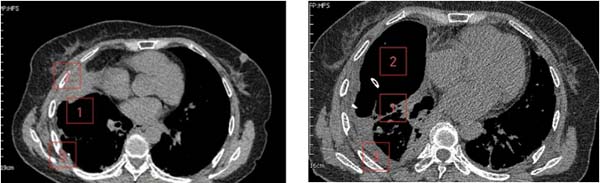

闭式引流前 闭式引流后

图中从左至右依次为

患者是一位61岁女性,诊断右侧巨型肺大疱已2年,近1周突发不明原因高热伴胸痛,体温最高达39.0℃。就诊于清华大学附属垂杨柳医院急诊科。经胸部CT检查,提示右侧巨型肺大疱(最大直径约15cm)内出现液平(最大直径约10cm),考虑疱内感染。虽经规范内科抗感染治疗,高热、胸痛症状未显著缓解,且进行性加重至无法脱离氧气支持,遂紧急转入我科进一步诊治。

在胸外科主任崔健指导下,胸外科医师赵洋乐即刻联系超声科,在其精准引导下实施右侧肺大疱内及右侧胸腔脓液闭式引流术,成功引流出超过1000ml坏死液体。术后患者体温迅速恢复正常,胸痛显著缓解,脱氧状态下可自如活动。